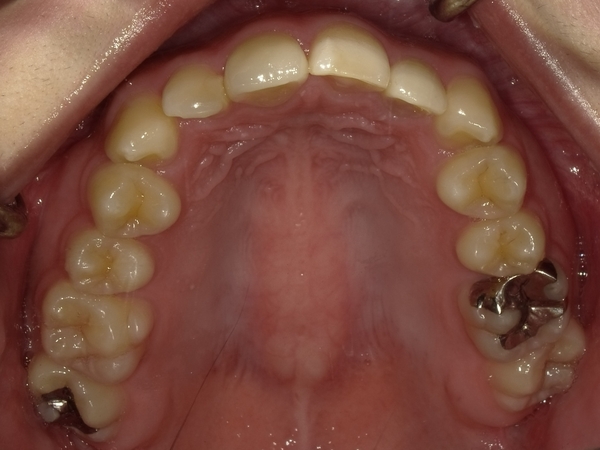

ガタガタとした歯並びや八重歯(叢生)CASE65